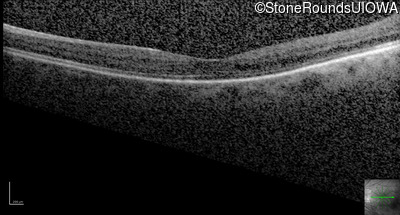

Optical Coherence Tomography - Right - 20/100 -1

Exemplar / OCT Stack

OCT Stack